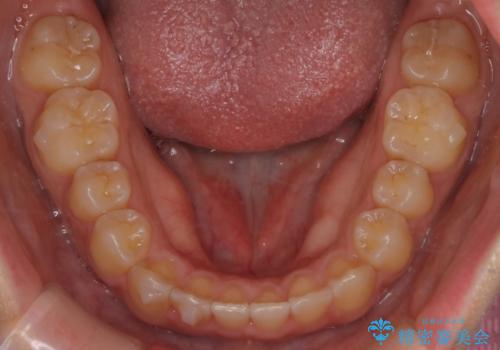

- 前歯の叢生を主訴に来院されました。非抜歯でインビザラインで治療をしました。

叢生はIPRをし、並べました。この患者様はオープンバイトだったため歯を並べる過程でかみ合わせも治しました。